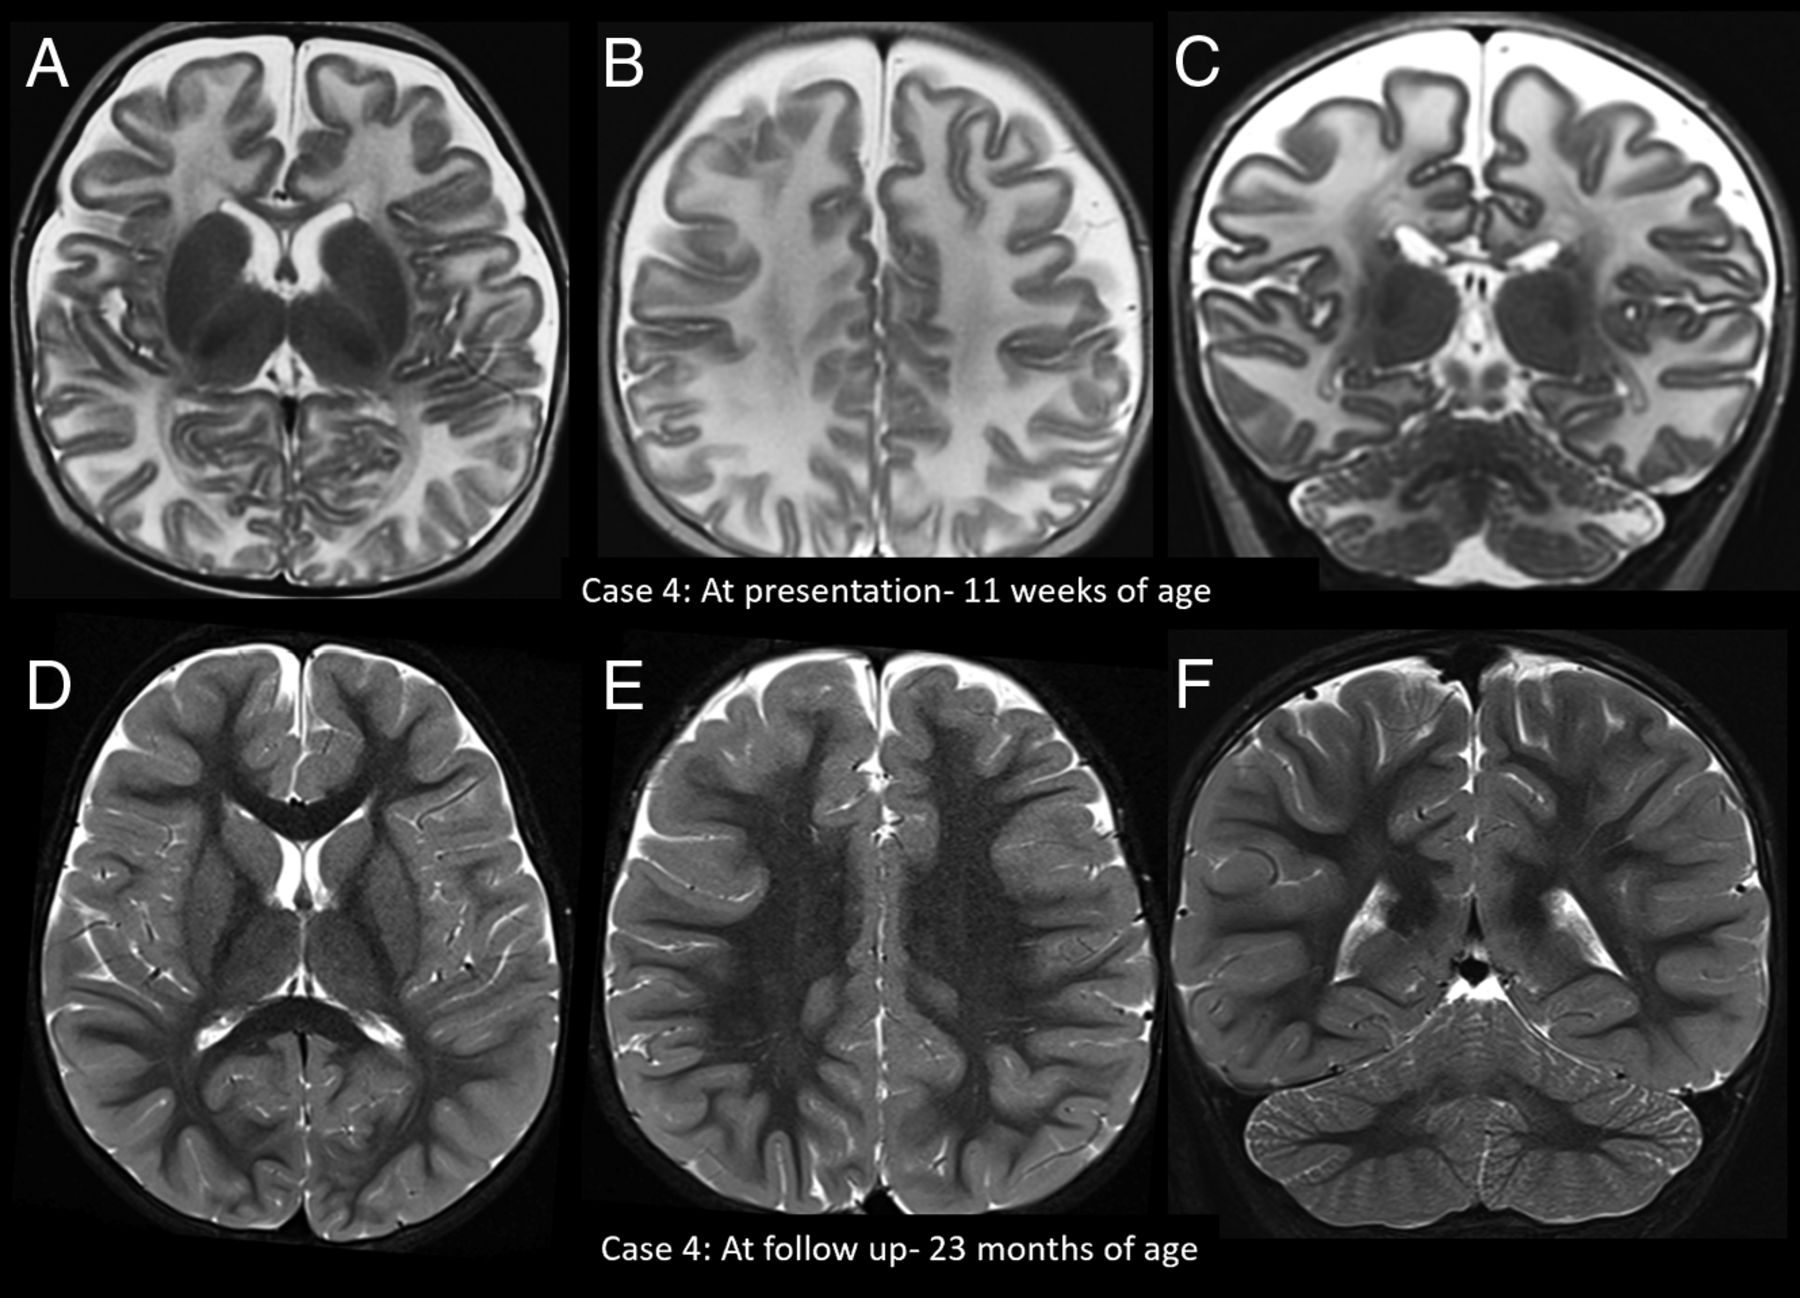

Imaging appearance and follow-up in the early infantile age group. Axial (A and B) and coronal (C) T2-weighted images in patient 4 at 11 weeks of age at the acute stage show diffuse white matter T2 hyperintensity. D–F, The findings fully resolved on treatment with biotin.

All patients were treated with biotin with doses ranging from 5 to 20 mg/day (median, 10 mg/day; interquartile range, 10–20 mg/day). Imaging following initiation of treatment was available in patients 4, 7, and 10 (at 2 years, 4 years, and 6 months of age, respectively), all of which showed resolution of swelling and signal abnormalities. Sequelae were only noted in patient 10 who showed frontal predominant cerebral atrophy and atrophy of the cerebellar semilunar lobules (Fig 2). On clinical follow-up, 3 patients (patients 1, 7, and 10) had sensorineural hearing loss, 2 (patients 1 and 5) had learning difficulties, and 1 (patient 10) had quadriparesis and strabismus.